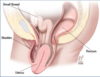

Label:

bladder

Location of uterus in relation to the bladder in females:

- uterus lays on top of urinary bladder.

- urge to urinate is entirely pressure driven.

- increased urge to urinate during pregnancy due to inreased uterine weight on the bladder.